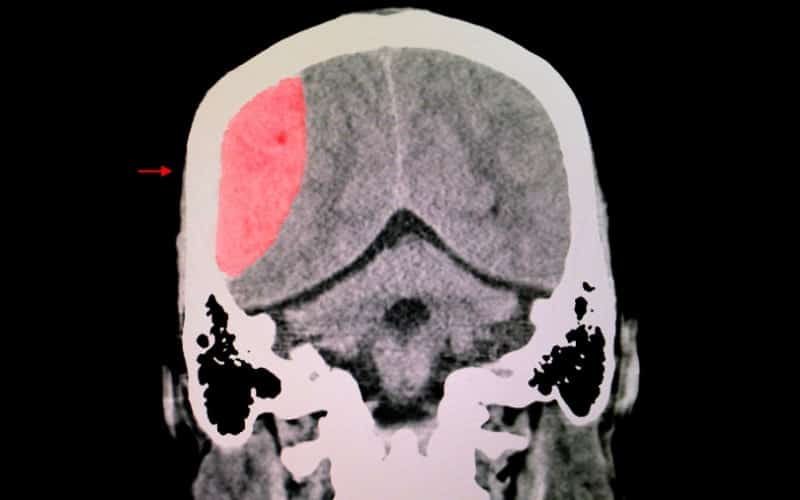

Traumatic brain injury (TBI), including concussion and head trauma, can cause immediate and long-lasting damage to the BBB.

The mechanical forces exerted on brain tissue during a traumatic event can directly disrupt the BBB, leading to increased permeability (aka leaky brain) and further neuronal injury.

In addition, chronic neuroinflammation is a common consequence of TBI, which can exacerbate BBB dysfunction and result in long-term cognitive impairments.

Repeated head traumas, such as those faced by athletes in contact sports, can result in breaches of the BBB, allowing damaging substances and pathogens to enter the brain.

This leaky brain is responsible for the many symptoms that concussions can cause.